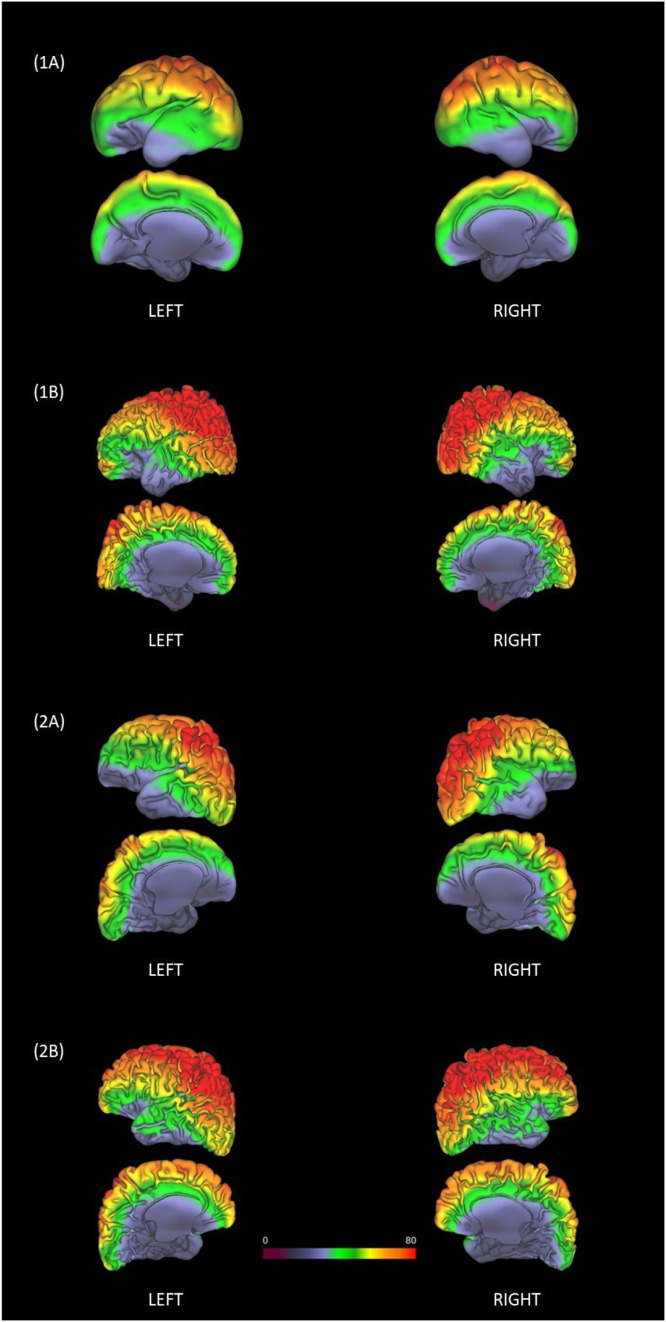

Fig. 3.

Impact of Head Position - Scanner Frame of Reference: Schaefer 40-week atlas resliced from individual space to MNI152 reference and overlayed on SNR-coil. Two example preterm participants with two sessions were chosen: (1A) Participant 1 at 29.9 weeks PMA (1B) Participant 1 at 38.4 weeks PMA. (2A) Participant 2 at 35.8 weeks PMA (2B) Participant 2 at 42.1 weeks PMA.

To test the hypothesis that differences in SNR due to head position affect connectome fingerprinting, an estimate of the SNR across the volume of the coil (SNR-coil) was derived and then used to estimate each individual's SNR based on location of their head (termed ‘SNR-group’). This was illustrated for two participants in the scanner frame of reference (Fig. 3) and in the brain frame of reference (Fig. 4).

Impact of Head Position - Brain Frame of Reference: SNR-coil resliced to individual space and mapped to mid-cortical thickness surfaces (T2w) (Left + Right). Two example preterm participants with two sessions were chosen: (1A) Participant 1 at 29.9 weeks PMA (1B) Participant 1 at 38.4 weeks PMA. (2A) Participant 2 at 35.8 weeks PMA (2B) Participant 2 at 42.1 weeks PMA.

The scanner frame of reference (Fig. 3) depicts the individual's Schaefer 40-week atlas resliced into MNI152 reference space and overlayed onto the SNR-coil. Head position and distance from the head coil directly are seen to influence the pattern of SNR across the brain. Using the brain frame of reference (Fig. 4), the SNR-coil was resliced to individual space and mapped to the mid-cortical thickness surface (T2w) using Connectome Workbench. Based on position in the head coil, it can be seen that the mid-cortical thickness surface has a variable pattern of SNR across the various sessions (preterm and term examples).